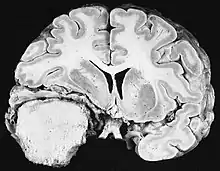

Ionizing radiation

Sources of ionizing radiation include medical imaging, and radon gas. Ionizing radiation is not a particularly strong mutagen.[74] Medical use of ionizing radiation is a growing source of radiation-induced cancers. Ionizing radiation may be used to treat other cancers, but this may, in some cases, induce a second form of cancer.[74] Radiation can cause cancer in most parts of the body, in all animals, and at any age, although radiation-induced solid tumors usually take 10–15 years, and can take up to 40 years, to become clinically manifest, and radiation-induced leukemias typically require 2–10 years to appear.[74] Radiation-induced meningiomas are an uncommon complication of cranial irradiation.[79] Some people, such as those with nevoid basal cell carcinoma syndrome or retinoblastoma, are more susceptible than average to developing cancer from radiation exposure.[74] Children and adolescents are twice as likely to develop radiation-induced leukemia as adults; radiation exposure before birth has ten times the effect.[74]

Ionizing radiation is also used in some kinds of medical imaging. In industrialized countries, medical imaging contributes almost as much radiation dose to the public as natural background radiation. Nuclear medicine techniques involve the injection of radioactive pharmaceuticals directly into the bloodstream. Radiotherapy deliberately deliver high doses of radiation to tumors and surrounding tissues as a form of disease treatment. It is estimated that 0.4% of cancers in 2007 in the United States are due to CTs performed in the past and that this may increase to as high as 1.5–2% with rates of CT usage during this same time period.[80]

Residential exposure to radon gas has similar cancer risks as passive smoking.[74] Low-dose exposures, such as living near a nuclear power plant, are generally believed to have no or very little effect on cancer development.[74] Radiation is a more potent source of cancer when it is combined with other cancer-causing agents, such as radon gas exposure plus smoking tobacco.[74]